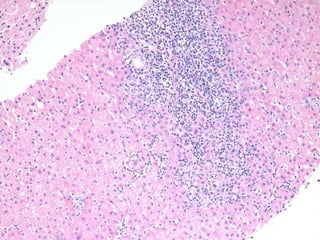

BS09-10453 55 yo, female.  Clinical history:  Elevated ALT/AST. Viral serologies negative.

BS09-10453:  Dx: Chronic hepatitis, with severe activity (bridging necrosis) and portal fibrosis, ? autoimmune hepatitis vs. drug/toxin mediated injury. Corresponds to: Modified Ishak stage 1/4 Metavir F1

BS09-10453 55 yo,female. Clinical history: Elevated ALT/AST. Viral serologies negative.

BS09-10453: Dx:Chronic hepatitis, with severe activity (bridging necrosis) and portal fibrosis, ? autoimmune hepatitis vs. drug/toxin mediated injury. Corresponds to: Modified Ishak stage 1/4 Metavir F1